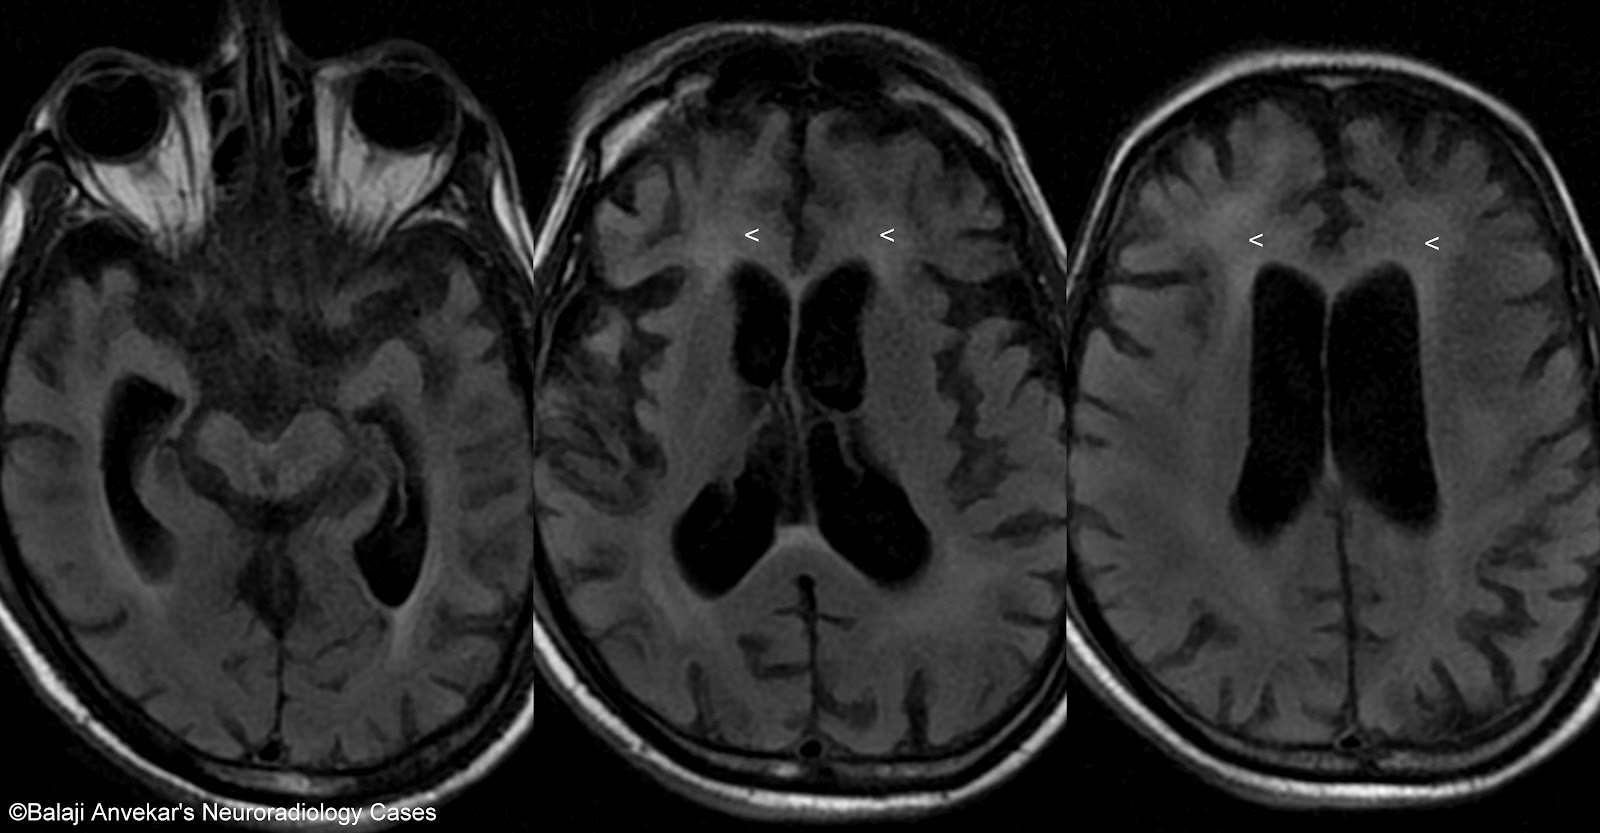

From radiologykey.com

Neuroimaging in the Brain in HIV1Infected Patients Radiology Key Hiv Brain Fog Finally, we address emerging considerations for cognitive health in hiv, including potential challenges surrounding efficacy and effects of hiv cure interventions related to hiv. Hiv and aids both cause a number of neurological complications, particularly if hiv goes untreated and is allowed to progress to aids. Hiv infection in the brain can also trigger an inflammation that may damage the. Hiv Brain Fog.

Neuroimaging in the Brain in HIV1Infected Patients Radiology Key Hiv Brain Fog How can i prevent hiv? Hiv prevention and testing am i infected? This can include difficulty concentrating, confusion, and. Hiv infection in the brain can also trigger an inflammation that may damage the brain and if left untreated can cause symptoms. Finally, we address emerging considerations for cognitive health in hiv, including potential challenges surrounding efficacy and effects of hiv. Hiv Brain Fog.

Brain atrophy in HIV/AIDS, MRI scans Stock Image C058/2245 Hiv Brain Fog Hiv prevention and testing am i infected? How can i prevent hiv? Hiv infection in the brain can also trigger an inflammation that may damage the brain and if left untreated can cause symptoms. Hiv and aids both cause a number of neurological complications, particularly if hiv goes untreated and is allowed to progress to aids. This can include difficulty. Hiv Brain Fog.